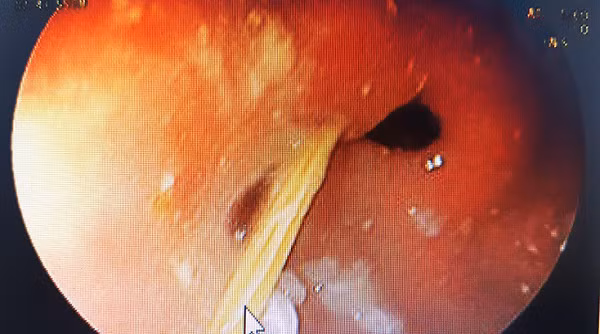

Trong quá trình phẫu thuật, các bác sĩ phát hiện ổ áp xe lớn, đường kính hơn 10 cm, nằm ở thùy gan trái và dính vào bờ cong nhỏ của dạ dày. Bên trong, có một chiếc tăm tre dài khoảng 5 cm đã cắm sâu vào nhu mô gan.

May mắn cho bệnh nhân là ổ áp xe còn khu trú tại gan chứ chưa vỡ có thể gây viêm phúc mạc (có thể nguy hiểm đến tính mạng bệnh nhân) điều này giúp quá trình phẫu thuật diễn ra thuận lợi hơn. Các bác sĩ đã cắt bỏ thùy gan trái kèm ổ áp xe và lấy dị vật. Sau phẫu thuật, bệnh nhân tỉnh táo, ổn định hồi phục nhanh chóng.